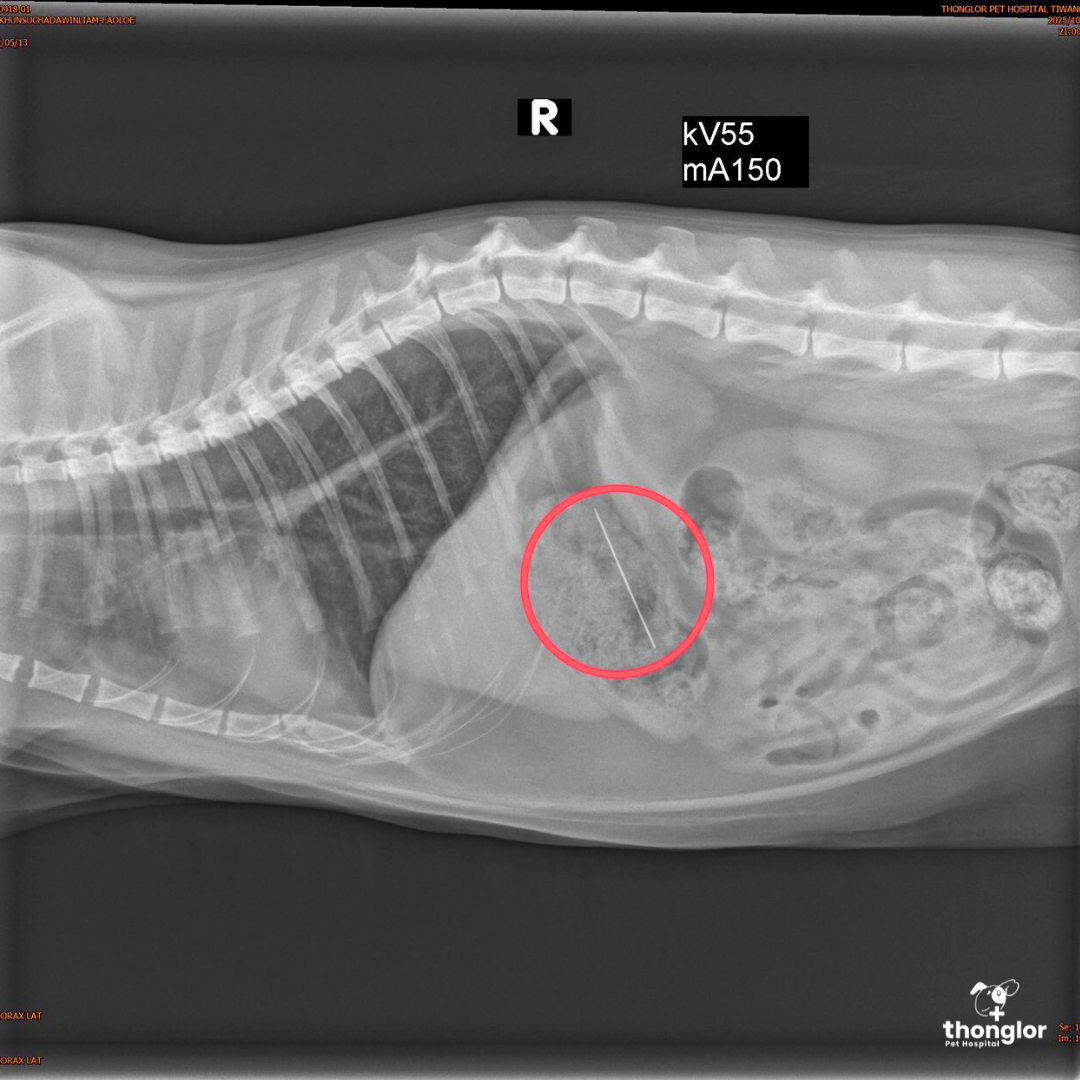

This was another case that made the team of vets and nurses hold their breath. The owner brought little STORMY to the hospital and reported that, "The cat accidentally swallowed a ’sewing needle’." A sewing needle is a dangerous foreign body that can cause perforation of the digestive tract at any moment, so it had to be removed immediately.

Upon arrival, the vet performed an X-ray right away and located the needle in the cat’s stomach. Instead of opting for open-abdominal surgery, the vet chose the special helper: "Endoscopic Surgery (Endoscope)". This technique allows the foreign object to be retrieved from the stomach without needing to open the pet’s abdomen. This technique not only safely saved the cat’s life but also minimized wounds and allowed for a much quicker recovery than open surgery.

After the endoscopy, STORMY was admitted for close observation in the ICU room for 1 night to ensure no complications occurred. The next day, the little one was safely discharged and went home!